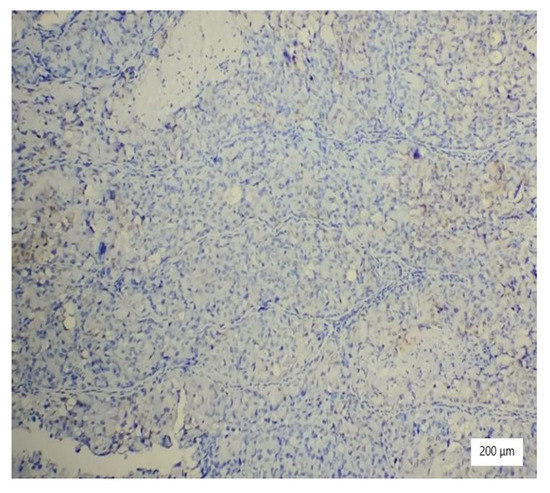

Figure 10. Negative vimentin in tumor cells (×100).